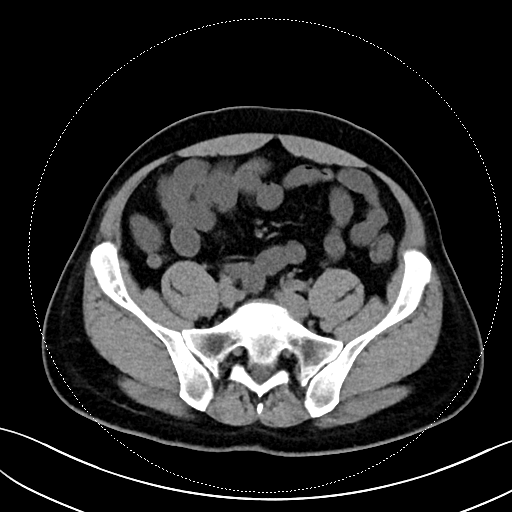

该患者的症状表现为钝痛,与进食、排便没有关联,也未出现发热、腹泻等伴随症状。在外院检查时,常规实验室检查如血常规、CRP、粪便钙卫蛋白均无异常,胃镜、结肠镜、胶囊内镜及超声内镜检查也未发现溃疡、肿瘤或克罗恩病的迹象。转诊至我院后,马师洋副教授团队另辟蹊径,对患者的腹部 CT 进行了细致入微的 “像素级” 阅片,并通过三维重建分析,敏锐地捕捉到阑尾根部呈现 “折角样” 扭曲,管腔局部狭窄且粘膜皱襞紊乱,虽无典型阑尾炎的周围脂肪条索、粪石等征象,但这一发现与患者的疼痛定位高度吻合,初步判断为非梗阻性阑尾功能障碍。

关键影像图片